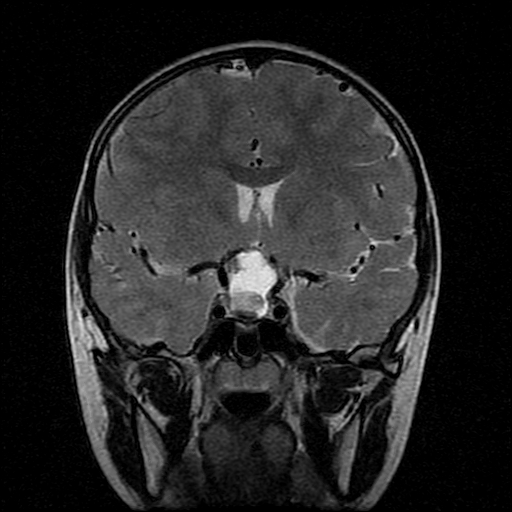

男性,12岁。反复头痛呕吐半月。脑积液无异常。病变部位ct值32hu,dwi无异常。

鞍上为主,累及鞍内,垂体受压位于鞍底。mri呈短t1、长t2信号,不太支持生殖细胞肿瘤,首考颅咽管瘤。

鞍内囊性占位性病变,t1wi、t2wi,均为高信号影。ct平扫为等密度。发病年龄较小。故首先考虑颅咽管瘤,可以做ct增强扫描